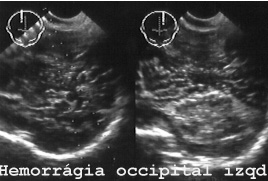

En la figura 64 hay una hemorragia occipitotemporal izquierda y edema en el lado contralateral.

64HEORRG.JPG (21529 bytes)

Fig 64